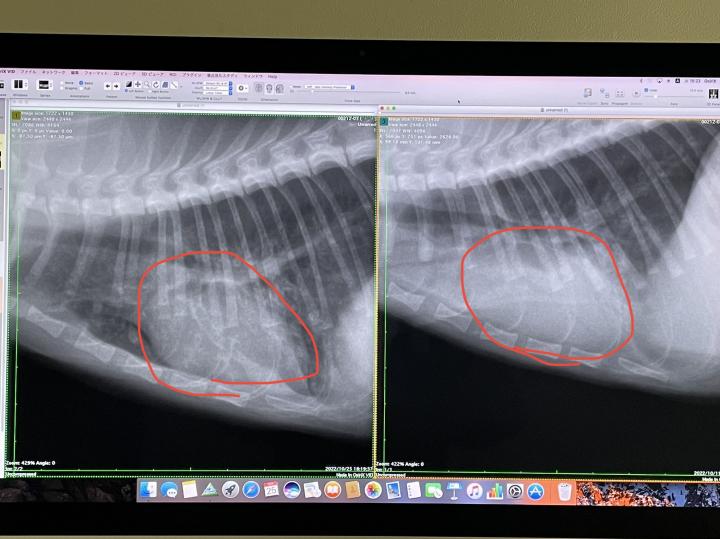

右退院時

左火曜日

赤マルの中の心臓の形がはっきり見えるようになりました